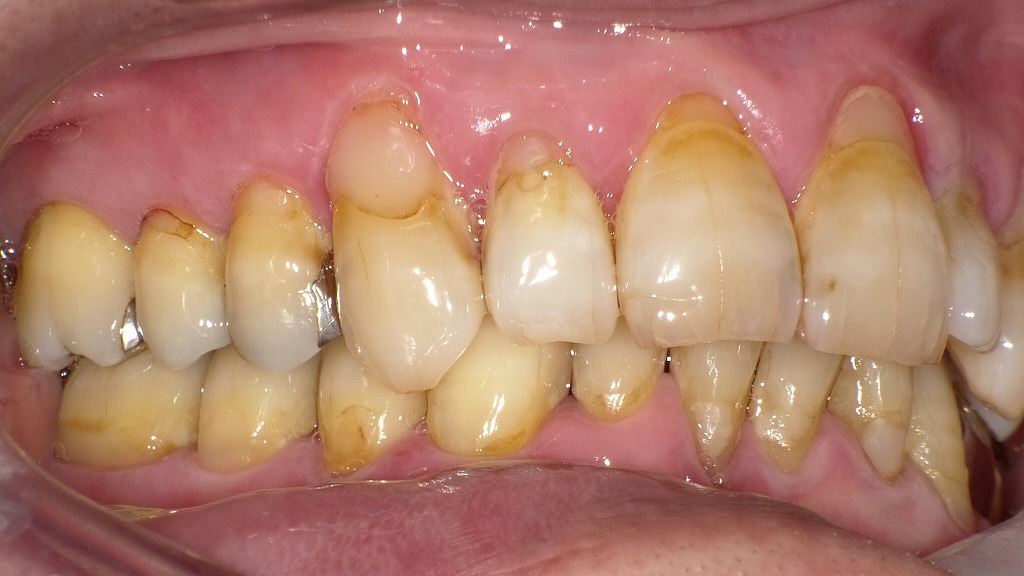

また治癒力が下がるため、炎症が長引きやすく、歯周病が進行しやすくなります。② 右側写真:縁下歯石と歯肉の炎症反応の増大

歯の根元にプラークと縁下歯石が多く付着し、歯肉が赤く腫脹。

糖尿病により炎症反応が増幅し、出血しやすい歯肉の典型例です。右側の画像では、以下の所見が明確です。

- 歯肉が丸く腫れ、縁下歯石による歯肉縁の赤みと出血

- 歯の根元に付着したプラーク・バイオフィルム

- 歯肉の引き締まりが弱く、糖尿病特有の浮腫状の歯肉がみられる

縁下歯石は歯周病を加速させるため、糖尿病患者では特に**早期のスケーリング・ルートプレーニング(SRP)**が重要です。

③ 左側写真:広範囲にわたる歯周炎の兆候

広範囲に歯肉の腫れと発赤があり、歯間部には隠れた出血点が多数。

血糖コントロール不良が歯周病の進行を加速させています。左側の画像でも、

- 歯頰側の歯肉がぷっくりと腫れている

- 歯間の歯肉が赤く、**隠れた出血ポイント(BOP)**が多数

- 歯の根元の茶色い付着物はプラーク~縁下歯石の混合

糖尿病による血流障害や免疫力低下により、炎症がさらに助長されている所見として典型的です。